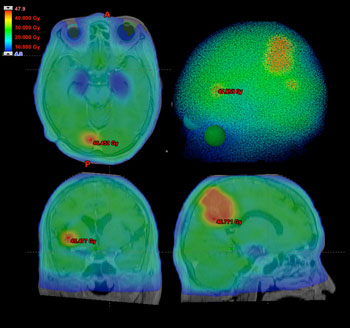

多発転移性脳腫瘍例に対するVMAT 治療計画例(5分割照射)

MRIで確認できた3カ所の病変に対して辺縁線量40Gy(8Gy/Fr.)を照射しつつ、

全脳に20Gy(4Gy/Fr.)照射。海馬の被曝線量は10Gy未満に抑えられており、

眼球レンズは被曝していない。

VMATを用いると、例えば多発脳転移症例において、転移病巣に対して大線量照射を行いつつ全脳に低線量照射を同時に行い、かつ、海馬の被曝を避けると言った照射も可能となります(図1)。多発転移例におけるガンマナイフ治療は、異所性再発の危険性や、意図に反して正常脳に高線量被曝部位(hot-spot)が生じる危険性がある一方、従来の全脳照射では海馬の被曝に伴う学習記憶能力の低下の危険を伴っていました。VMATでは、脳全体に対する治療計画を作成するため、意図に反するhot-spotが生じる危険が少なく、また海馬の被曝を避けることで学習記憶能力低下を予防できると期待されています(海馬への転移発生の頻度は極めて低いことも報告されています)。この照射法では分割回数も自由に設定できるため、病変の大きさに対応した照射も可能です。さらに、従来のIMRTに比較して治療時間が短いのも特徴で、例えば図1の転移例に対する照射は1回数分で終了します。